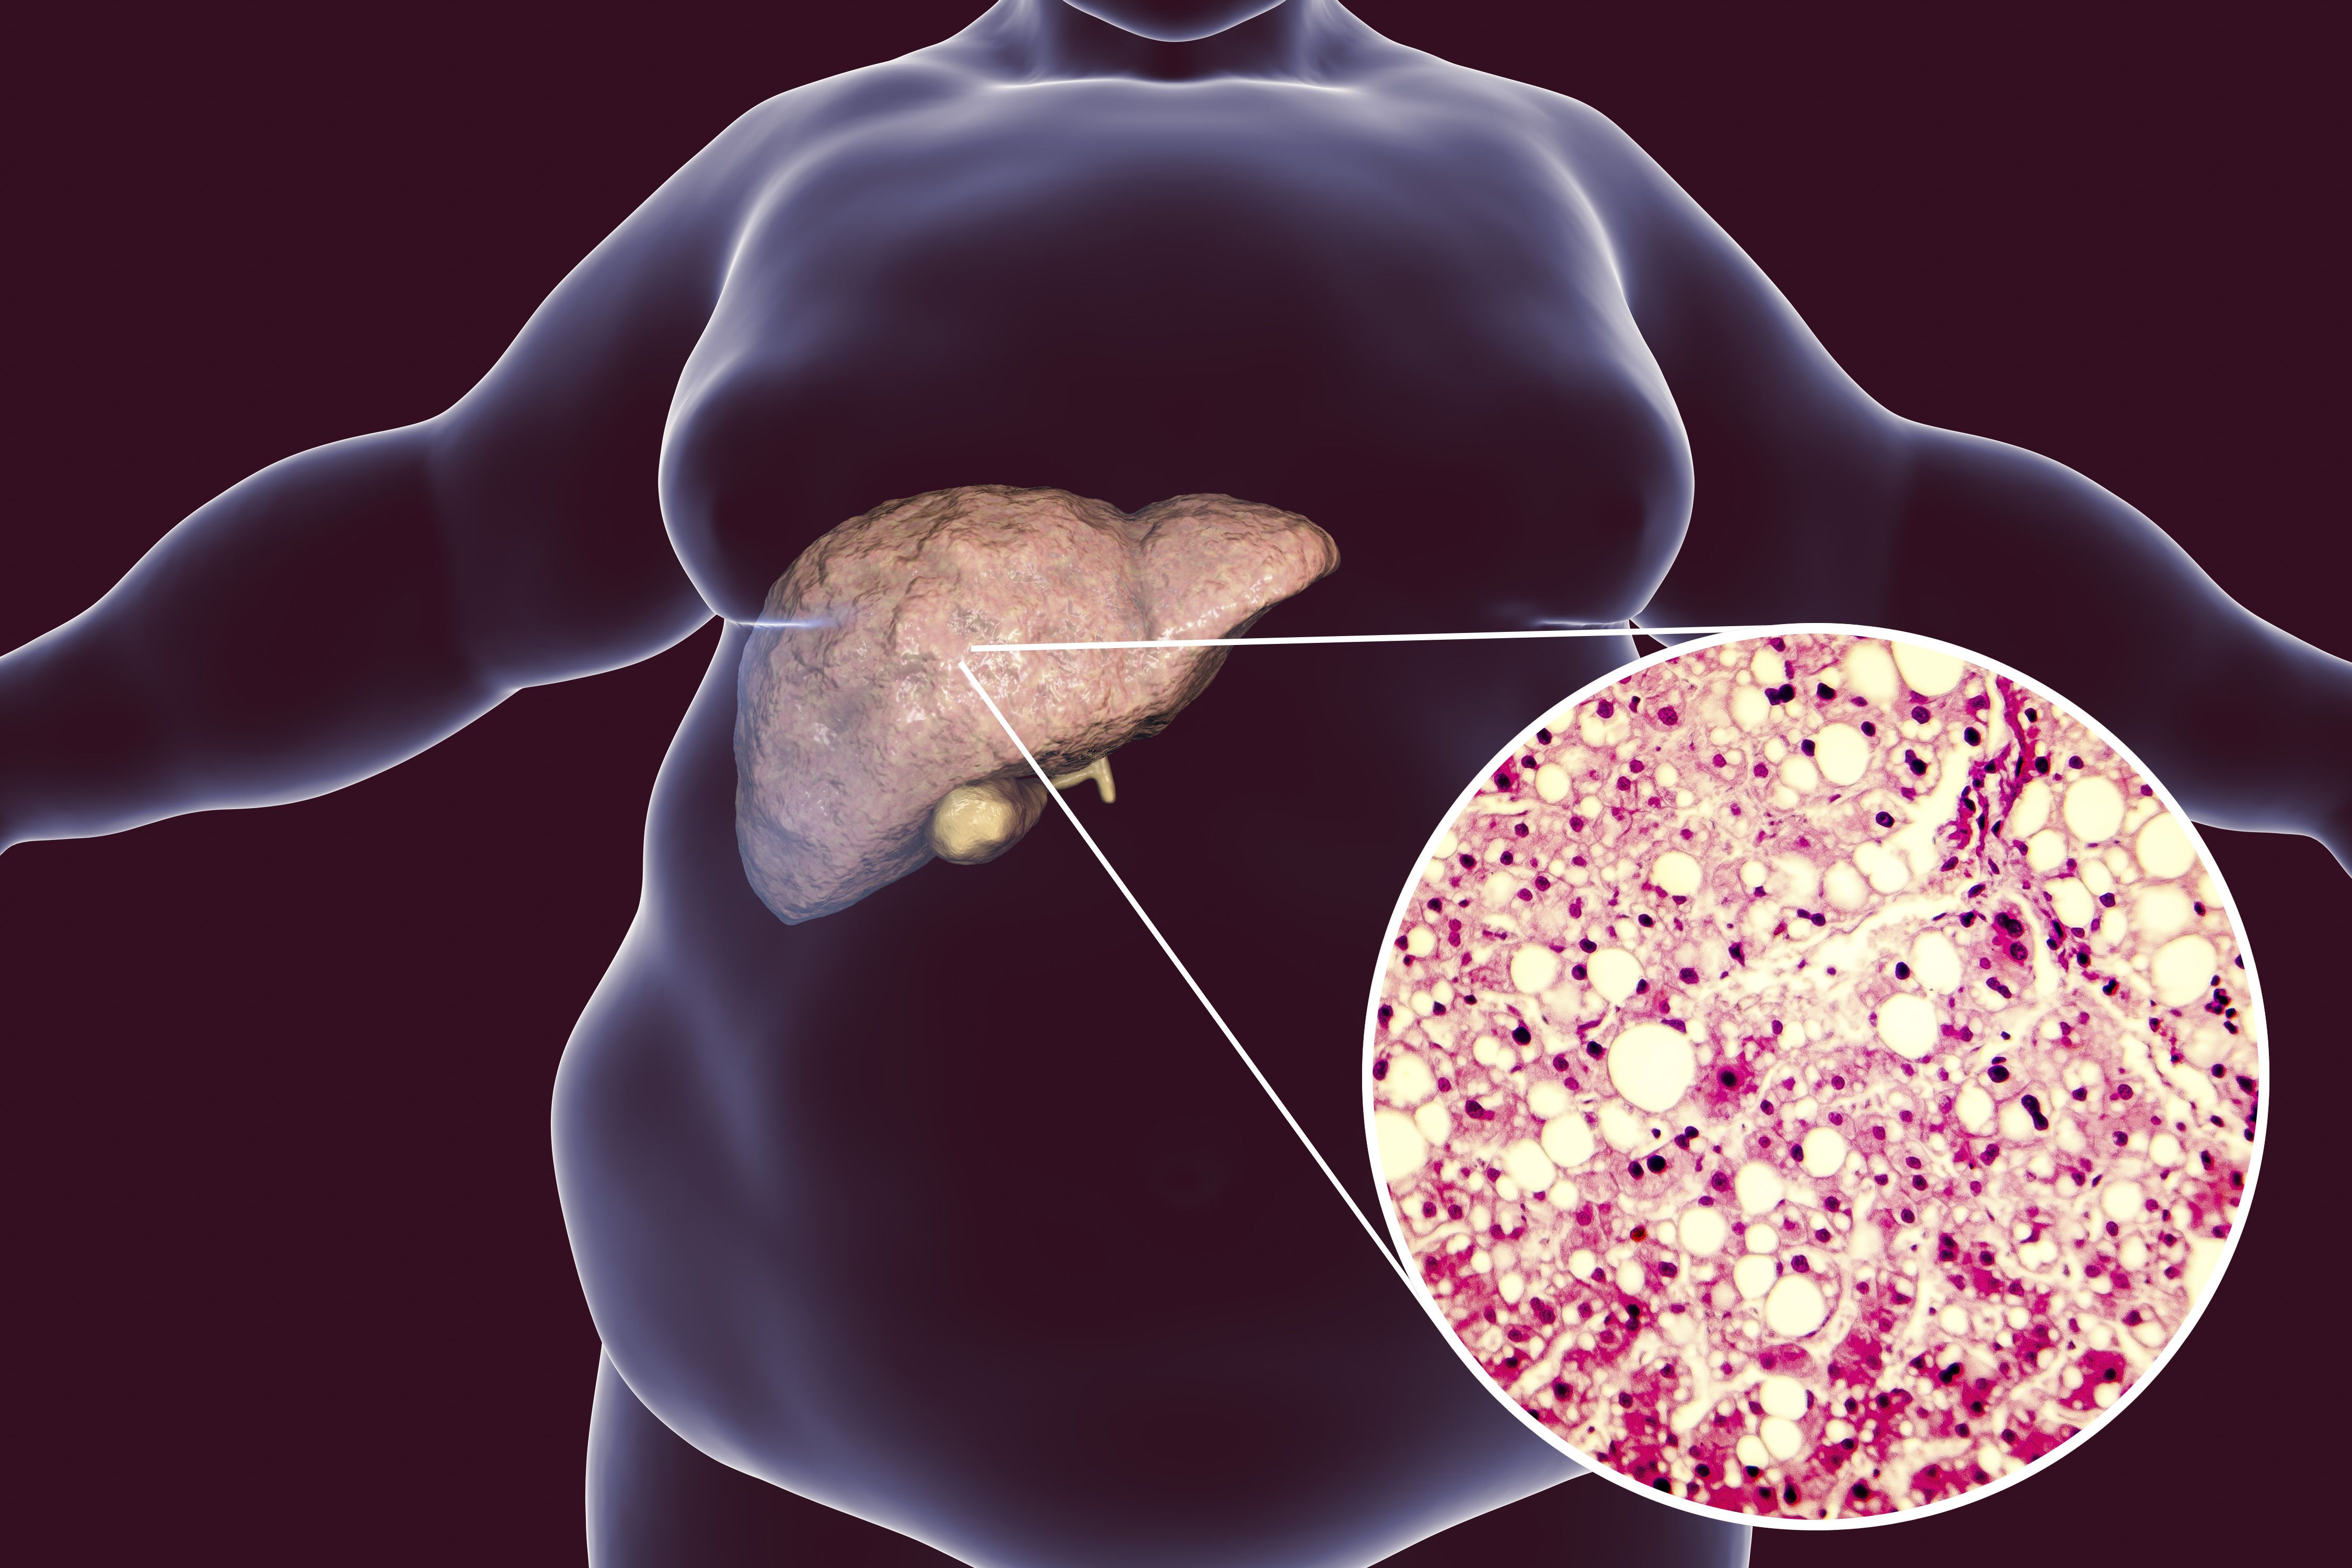

Практические советы по лечению ожирения печени в домашних условиях

Узнайте, как можно эффективно и безопасно лечить ожирение печени в домашних условиях с помощью простых рекомендаций и советов. Избавьтесь от этого заболевания и улучшите свое здоровье с легкостью.

Жировой ГЕПАТОЗ : причины, симптомы, ДИЕТА и ЛЕЧЕНИЕ. Ожирение печени: что делать.